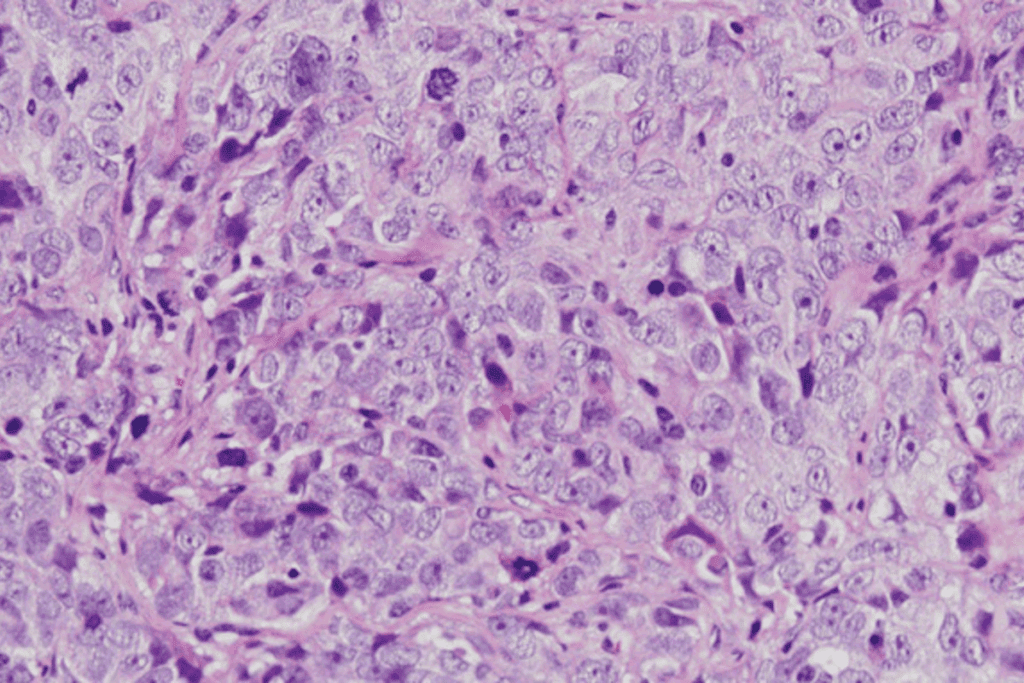

Red Flags in MRI Results: When to Be Concerned

MRI scans are a powerful tool for diagnosing health issues. Some results can signal serious problems that need quick action. It’s important for patients to know when to worry about their health based on MRI results.

Signs That Indicate Serious Conditions

Certain MRI findings can point to serious health issues. These include:

- Unidentified Bright Objects (UBOs): These bright spots on MRI scans can mean anything from harmless to serious.

- Masses or Tumors: MRI scans can spot tumors in the brain, spine, and organs.

- Spinal Cord Compression: This is a medical emergency that needs immediate care.

Not all MRI findings are serious. But, some need quick attention.